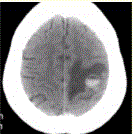

问题 患者女,55岁,右侧肢体无力3d。头颅CT显示如下图。 可能的诊断为(提示2d后复查,CT显示如下图。)

选项 A.急性脑血肿 B.转移瘤伴出血 C.胶质瘤伴出血 D.少枝胶质细胞瘤伴出血 E.血液系统病变伴脑出血 F.脑脓肿 G.血管畸形伴出血

答案 ABCEG